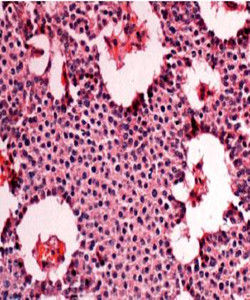

病理生理肉眼觀腫瘤的切面大都呈灰白色或粉紅色,質地較正常組織為軟,血供豐富。多數腫瘤的邊界清楚但無明顯包膜;部分腫瘤有包膜或假包膜。胰島素瘤是各種胰島細胞瘤中最常見的一種,約50%的腫瘤為單純的β-細胞瘤,但有些是含有α-、δ-,PP和G細胞的混合性腫瘤,目前無論是光鏡還是電鏡都很難鑑別瘤細胞的具體類型。光鏡下瘤細胞與正常的β-細胞頗為相似,呈多角形、立方形或柱狀,胞核呈圓或卵圓形,核分裂罕見。瘤細胞的組織學排列類型不一,有實體或瀰漫結構的、呈腺泡或管樣結構、小梁或腦回狀結構的等。電鏡下瘤細胞內有豐富的功能性細胞器,胞漿中線粒體豐富,在部分腫瘤的瘤細胞內還含有典型的β-細胞分泌顆粒,但由於並非所有的胰島素瘤細胞內部均含有分泌顆粒,而且其他類型的胰島細胞中也可出現高密度的分泌顆粒,故電鏡下仍很難判斷瘤細胞的具體類型。

免疫組織化學填補了光鏡和電鏡的不足,它是迄今為止確診和鑑別胰島腫瘤的最好的技術。此法利用特異的抗胰島素抗體,可使絕大多數的β-細胞瘤呈免疫陽性反應,是目前胰島素瘤病理學診斷的主要依據。惡性胰島素瘤單從形態上不易與良性者區分,雖然鏡下有時可見細胞核分裂,但目前診斷惡性胰島素瘤的可靠依據是腫瘤轉移或明顯的周圍組織浸潤。β-細胞增生有瀰漫性和結節性兩種,有時可伴微小腺瘤,光鏡下表現為局部胰島的體積增大或數量增多。